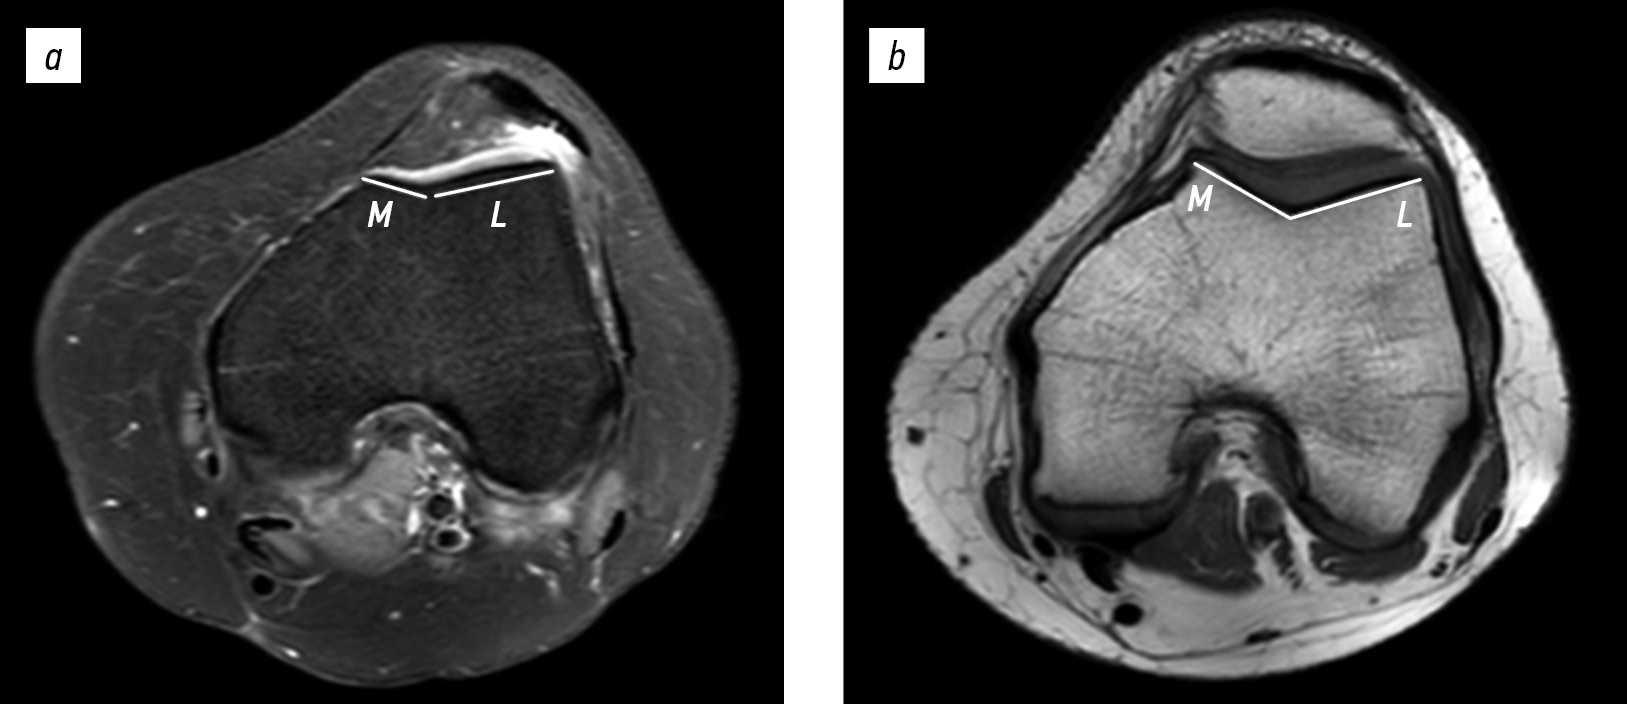

Moreover, MRI was used to determine the presence of free osteochondral bodies and signs of medial patellar margin fracture, and the patellotrochlear index was analyzed. On lateral projection, the height of the patellar articular surface (B) and portion of the trochlear groove articulating with the patella (A) were measured. The ratio А/В × 100% was calculated, with values <12.5% considered normal according to scientific data (Fig. 4) [17].

Fig. 4. Patellotrochlear index on magnetic resonance imaging: a, 16-year-old female with patellar instability. Patellotrochlear index value: 11.4%; b, 15-year-old male with anterior cruciate ligament injury. Patellotrochlear index value: 39.1%. A, length of the trochlear articular surface in contact with the patellar articular surface; B, length of the patellar articular surface (patellar height).